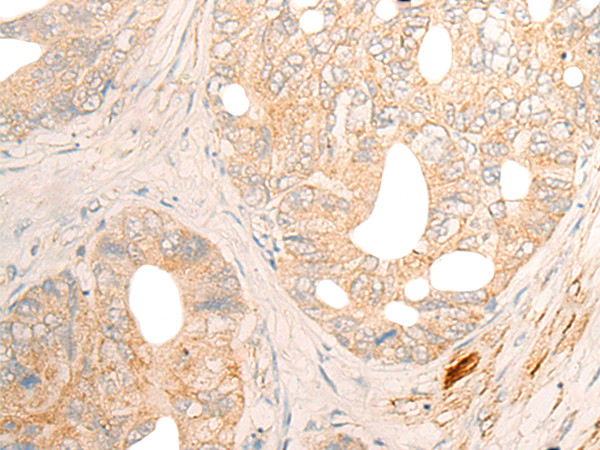

分类: 科研抗体货号: P06360别名: SPG28; PAPLA1; PA-PLA1应用: IHC反应种属: Human